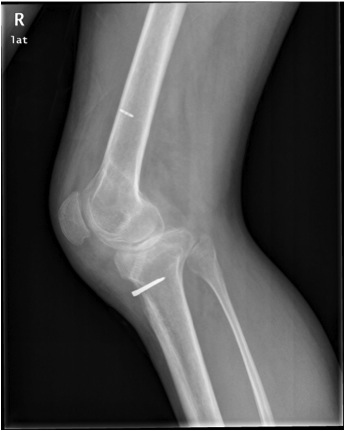

Fracture

Patella fracture

Tibial fracture

If using back up fixation such as a fracture, ensure sufficient distance from tibial tunnel

Alternatively, use a screw-post fixation